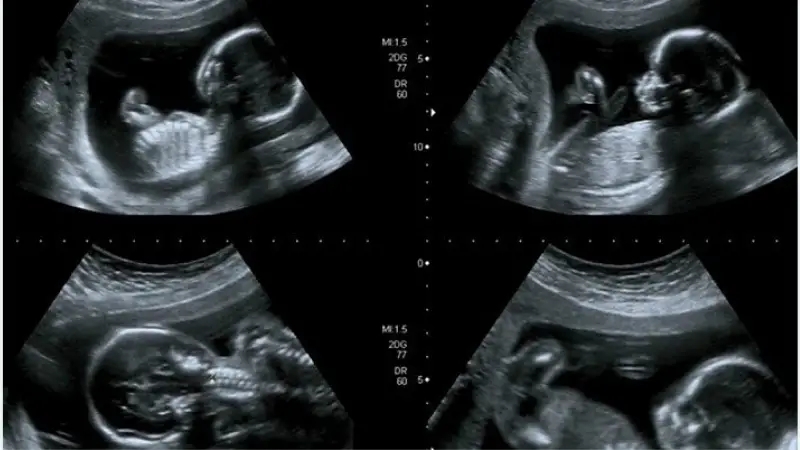

«غربالگری اول»، ترکیبی از آزمایش خون و سونوگرافی است که اطلاعات ارزشمندی درباره سلامت جنین و احتمال بروز ناهنجاریهایی مانند مشکلات قلبی یا سندرم داون ارائه میدهد. باید توجه داشت که وجود ناهنجاری در نتایج غربالگری سه ماهه اول بارداری به معنای قطعی وجود مشکلات ژنتیکی در جنین نیست؛ اما یکی از مراحل مهم در دوران بارداری است که علاوه بر شناسایی سندرم داون، امکان تشخیص ناهنجاریهای جنینی دیگر را نیز فراهم میکند. این آزمایش که معمولاً در هفتههای یازدهم تا سیزدهم بارداری انجام میشود، بخشی از روند مراقبتهای دوران بارداری است که به شما اطمینان میدهد جنین در سلامت کامل قرار دارد. اگر شما نیز در سه ماهه اول دوره بارداری خود قرار دارید، در این مقاله از مجله سلامت ایمپو همراه ما باشید تا با «آزمایش غربالگری اول»، آزمایشها، تفاسیر و همچنین «اعداد نرمال آزمایش غربالگری اول» بیشتر آشنا شوید.

یکی از مهمترین معاینات و آزمایشهای دوران بارداری، غربالگری اول است که معمولاً بین 11 هفته و ۳ روز تا ۱۳ هفته و ۶ روز انجام میشود. آزمایش غربالگری اول، ترکیبی از آزمایش خون و سونوگرافی است که هدف اصلی آن، سنجش شرایط مادر و جنین و ارائه اطلاعاتی در مورد سلامت جنین و برخی ناهنجاریهای احتمالی است. در غربالگری سه ماهه اول، نتایج آزمایش خون و سونوگرافی، وجود مشکلات احتمالی چون اختلالات ژنتیکی را شناسایی کرده و به شما کمک میکند که از سلامت و رشد مناسب جنین خود مطمئن شوید.

آزمایش غربالگری اول شامل نمونهگیری خون از مادر است که در کمتر از ۱۰ دقیقه انجام میشود. پس از آن، نمونه خون توسط تکنسین آزمایشگاه به محل آزمایش منتقل میشود. علاوه بر آزمایش خون، سونوگرافی غربالگری اول نیز توسط پزشک متخصص انجام میشود که معمولاً بین ۲۰ تا ۴۰ دقیقه به طول میانجامد.

سونوگرافی NT: این سونوگرافی ضخامت پوست ناحیه پشت گردن جنین را اندازهگیری میکند. پزشک میتواند با بررسی این ضخامت، برخی از نقصهای مادرزادی مانند سندرم داون را تشخیص دهد. بهترین زمان برای انجام این غربالگری اواخر سه ماهه اول بارداری و بین هفته یازده و هفته سیزدهم بارداری است. همراه با سونوگرافی، آزمایشهای خون نیز انجام میشوند. برای اطلاعات بیشتر راهنما جامع سونوگرافی NT را میتوانید مطالعه کنید.

در سونوگرافی nt (شفافیت نوکال)، مقدار مایع موجود در ناحیه پشت گردن جنین اندازهگیری میشود. به طور طبیعی، در همه جنینها مقداری مایع در این ناحیه دیده میشود؛ اما در جنینهای مبتلا به سندرم داون، مقدار مایع ناحیه پشت گردن معمولاً بیشتر است. از همین رو، اندازهگیری NT میتواند نشاندهنده ریسکهای مرتبط با اختلالات کروموزومی و شرایط ژنتیکی دیگر باشد.

در این سونوگرافی، اگر مقدار مایع پشت گردن جنین ۲.۵ میلیمتر یا کمتر از آن باشد، این عدد طبیعی تلقی میشود؛ درحالیکه مقادیر بالاتر از این حد ممکن است غیرطبیعی باشد. در این شرایط پزشک برای بررسی بیشتر ممکن است آزمایش ژنتیک سه ماهه اول بارداری را تجویز کند.